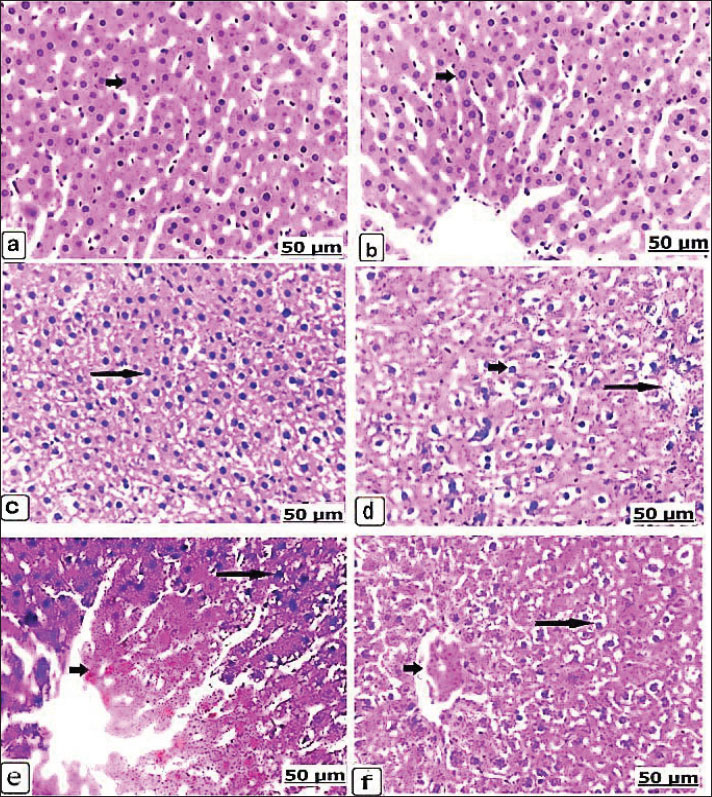

After 14 days, the microscopic sections of the liver from the control groups of non-pregnant and pregnant rats showed normal histological arrangements of the hepatic cords enclosed with intact hepatocytes (Fig. 2a,b). The liver of the non-pregnant group received 625 µg dexamethasone, showed hypertrophy of the hepatocytes with large, condensed nuclei (Fig. 2c). Pregnant animals, while receiving the same dose, manifested necrosis and vacuolar degeneration of the hepatocytes with interstitial hemorrhage (Fig. 2d). By an increasing dexamethasone concentration to 125 × 10 µg, the histological changes become more severe; however, the non-pregnant animals recorded severe hemorrhage with red blood cell infiltration, in addition to hepatic necrosis with acidophilic cells (Fig. 2e). Therefore, pregnant animals showed vacuolar degeneration of the hepatocytes with congestion and central vein dilatation (Fig. 2f). The stained microscopic liver sections after 21 days showed normal hepatic parenchyma not only in the control non-pregnant but also in the control pregnancy (Fig. 3a,b). When the non-pregnant group, when received 625 µg of dexamethasone for 21 days, congestion with dilatation of the blood vessels, liver necrosis, and acidophilia were observed (Fig. 3c). Similarly, after the same concentration of dexamethasone was administered, pregnant rats exhibited hepatic vacuolation with scattered lesions (Fig. 3d).

Fig. 2. (a–f). Light photomicrograph of the liver of the control and experimental groups for 14 days, stained with hematoxylin and eosin. Control non-pregnant C1(14) showing normally arranged hepatocytes and intact vasculature (arrow) (a) Pregnant control A1(14) showing normally organized hepatic cords (arrow) (b). Group D1(14) received 625 μg of dexamethasone, showing hypertrophied hepatocytes with enlarged and condensed nuclei (arrow) (c). Group B1(14) received 625 μg of dexamethasone (d). Necrosis and vacuolar degeneration of the hepatocytes (short arrow) with interstitial hemorrhage (long arrow). Group D2(14) received 125 × 10 μg of dexamethasone and showed severe hemorrhage with red blood cell infiltration (short arrow) and hepatic necrosis with acidophilic cells (long arrow) (e). Group B2(14) received 125 × 10 μg of dexamethasone, showing hepatocyte vacuolar degeneration (long arrow) with congestion and central vein dilatation (short arrow) (f).